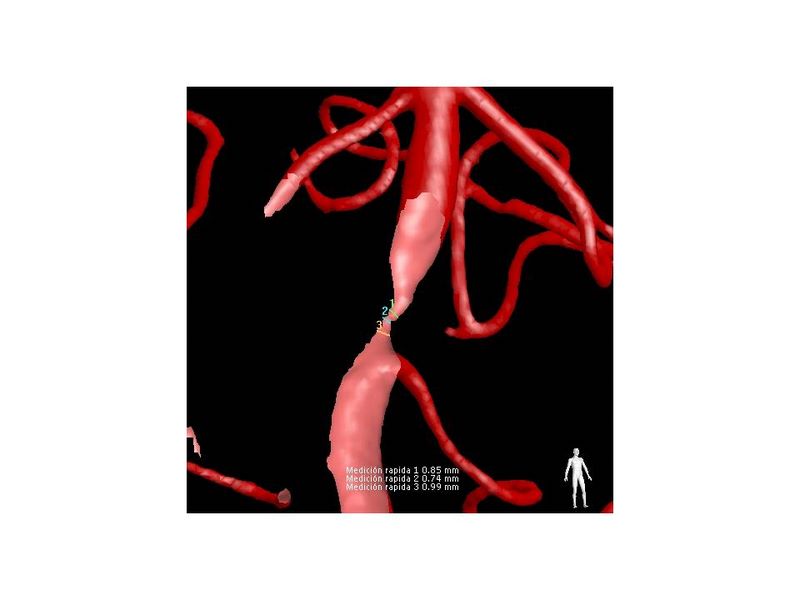

Estenosis Basilar